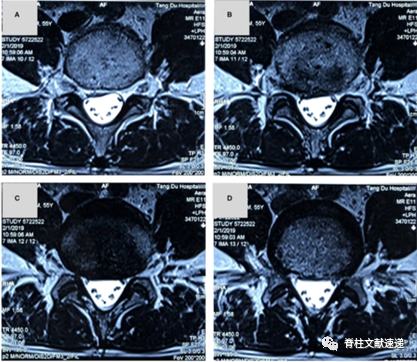

最近就诊病人中存在的坐骨神经带状疱疹患者。中年女性,左侧小腿和足面疼痛20天,夜间痛明显,查体直腿抬高试验阴性,可见膝关节及小腿外侧和足踝部水泡和皮损痕迹,追问病史得知疼痛后4天曾起水泡和皮肤破损,见下图。给予抗病毒和加巴喷丁治疗。1周后症状缓解。